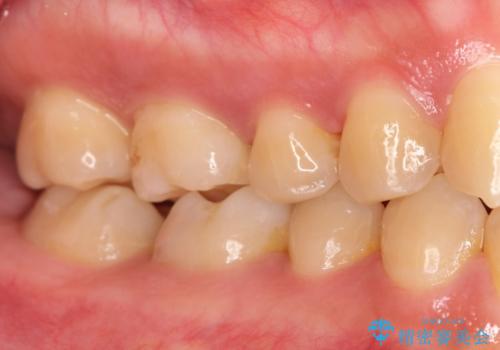

奥歯が痛い。根管治療~オールセラミッククラウン

- 奥歯の痛みを主訴に来院されました。

検査の結果、神経は保存不可能と診断されたため、根管治療~オールセラミッククラウンによる治療を行いました。